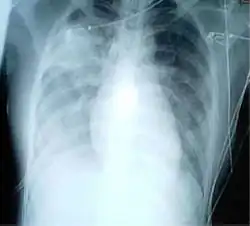

A chest radiograph is frequently used in diagnosis.[23] In people with mild disease, imaging is needed only in those with potential complications, those not having improved with treatment, or those in which the cause is uncertain.[23][69] If a person is sufficiently sick to require hospitalization, a chest radiograph is recommended.[69] Findings do not always match the severity of disease and do not reliably separate between bacterial and viral infection.[23]

X-ray presentations of pneumonia may be classified as lobar pneumonia, bronchopneumonia, lobular pneumonia, and interstitial pneumonia.[75] Bacterial, community-acquired pneumonia classically show lung consolidation of one lung segmental lobe, which is known as lobar pneumonia.[42] However, findings may vary, and other patterns are common in other types of pneumonia.[42] Aspiration pneumonia may present with bilateral opacities primarily in the bases of the lungs and on the right side.[42] Radiographs of viral pneumonia may appear normal, appear hyper-inflated, have bilateral patchy areas, or present similar to bacterial pneumonia with lobar consolidation.[42] Radiologic findings may not be present in the early stages of the disease, especially in the presence of dehydration, or may be difficult to interpret in the obese or those with a history of lung disease.[24] Complications such as pleural effusion may also be found on chest radiographs. Laterolateral chest radiographs can increase the diagnostic accuracy of lung consolidation and pleural effusion.[41]